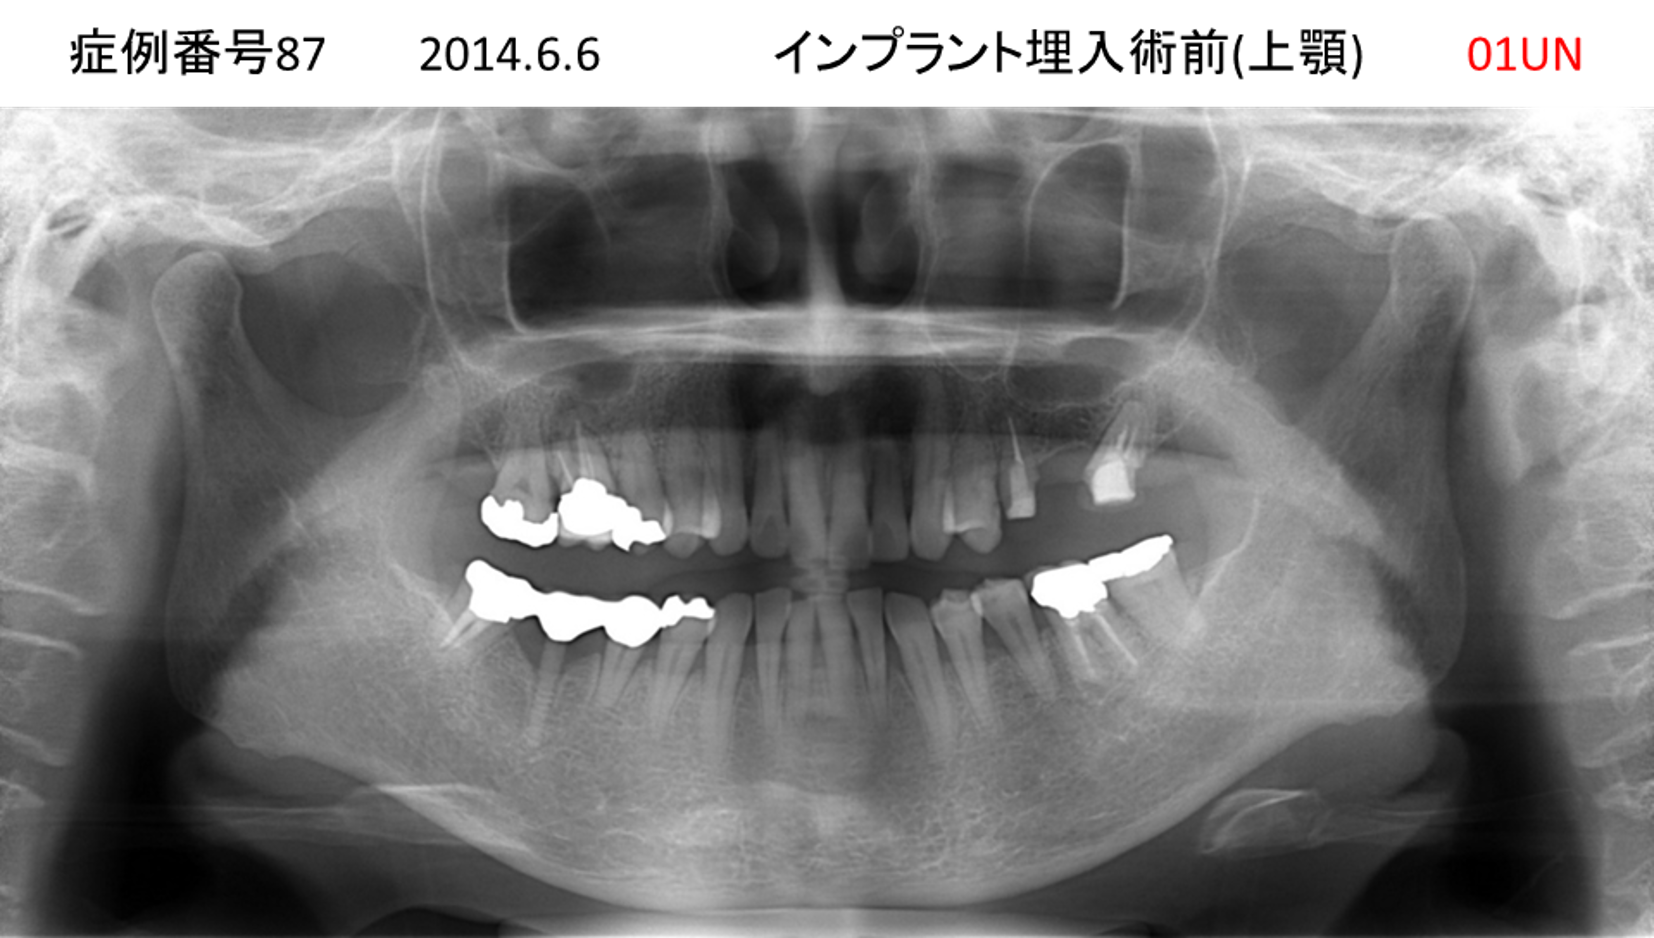

食事ができない/噛めない患者様のインプラント症例

| 治療名称 |

インプラント |

| 治療費用 |

540万円+税 |

| 治療期間 |

6か月 |

| 患者さんの症状(主訴) |

食事ができない。噛めない。上の前歯が揺れてきた。入れ歯がつらい。 |

| 治療内容 |

サイナスリフト、インプラント |

| 治療結果 |

なんでも食べられるようになった。力が入る(全身)ようになった。 |

| 治療の注意点(リスク/副作用) |

インプラントが壊れたら再治療が必要 |